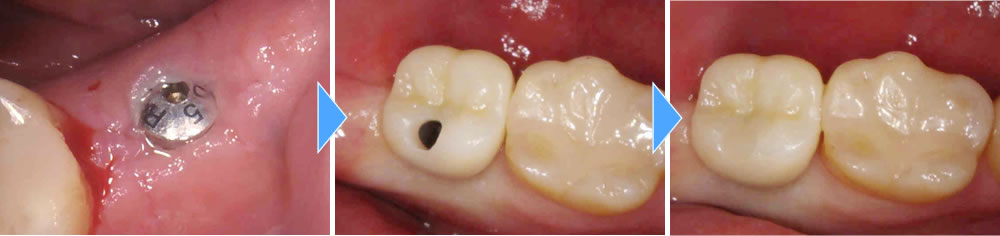

インプラント手術の実施

歯根破折のため、骨の欠損範囲が大きく、抜歯後半年ほど時間を置いてからインプラント埋入のオペをしました。インプラント埋入と同時に骨造成(骨を増やす処置)も行いました。

上部構造の装着・治療完了

インプラントと顎骨の結合期間を経て、製作した上部構造を装着。最終的な咬み合わせを調整して治療完了となりました。

術後は他の歯と変わりなくかたいものまでしっかりと噛むことができるようになり、大変満足していただいております。